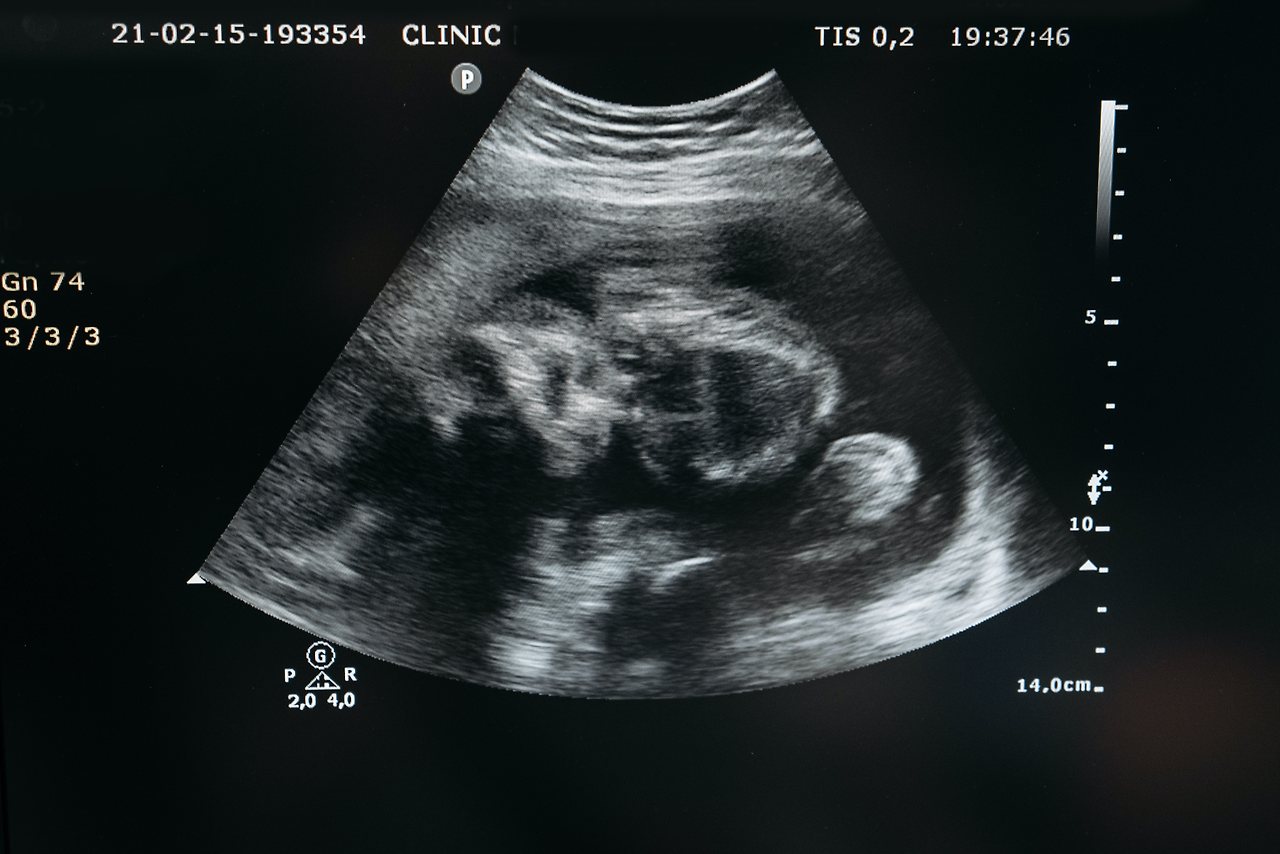

한국식 나이 계산법으로 태중에서의 10개월을 한 살로 쳐주는 것은 대단한 의미를 가진다.

사람은 태중에서 의 만 9개월이 진화론적인 계산에 따르면 36억 년의 진화과정에 해당되는 것이다.

이 밤손님은 9개월 동안 여자의 몸에서 머무는 동안 36억 년의 긴 신성한 생명탄생 과정을 선물로 받는다.

엄마의 몸속에서 보내는 9개월의 밤을 통해 아기는 완벽한 자율적 존재로 탄생한다.

이 밤손님은 9개월 동안 36억 년의 진화적 시간만 가져온 것이 아니다.

137억 년이라는 우주의 역사를 아우르는 몸의 구성요소를 가지고 36억 년이라는 생명 탄생과정을 겪어내는 9개월은 사람의 인생에서 가장 밀도 있는 삶을 살아온 신성한 기간이다.

태중에서의 만 9달 동안, 아기는 자신이 살아갈 100년을 대비해 필요한 모든 능력을 다 가지고 태어난다.